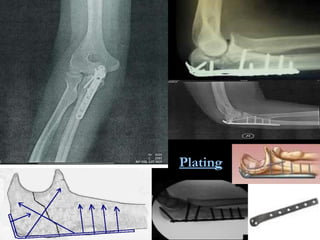

Plating

Fractures with significant displacement (>2 mm) or comminution may require surg ical intervention. Excision and triceps advancement may be indicated for severely comminuted fractu r es or for patients with osteoporotic bone. ORIF - for displaced intra- articu lar fractures. Intramedullary screw fixation , with or without a wire or cable, is the most secure. Plate fixation for extensive comminuted or unstable oblique fractures not amenable to other types of treatment. for an associated coronoid fracture